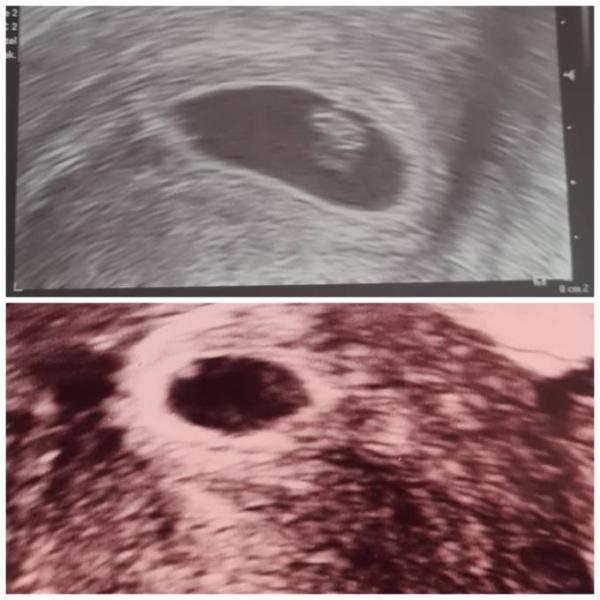

Ich hatte aufgrund von braunen schmierblutungen einen Ultraschall bei meiner gyn. in der 5+5 ssw. Die Ärztin meinte das alles normal sei. Ich hab aber immernoch bedenken. 6+4ssw hatte ich einen Ultraschall bei der Kinderwunsch Klinik, da hatte die Ärztin nichts gesagt außer das alles okay sei. Anhand des Ultraschalls, hat sich der Embryo entwickelt was positiv ist oder? Wovon kann die Schmierblutung kommen? Die ist weniger geworden aber ich hab die nun schon mehr als 1 Woche.